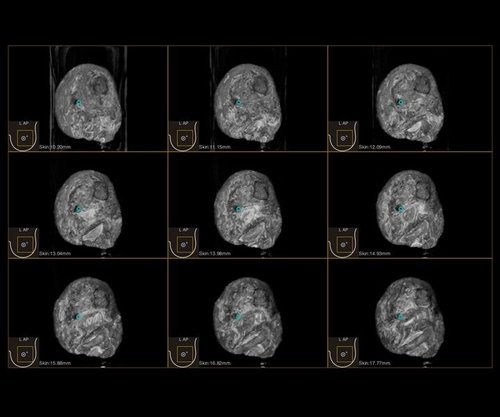

Das IBUS 60 ist ein intelligentes Brust-Vollvolumen-Ultraschallsystem der Marke SIUI.

Das IBUS 60 zeichnet sich durch Sicherheit und Komfort aus. Es bietet ein hochauflösendes Bild und reduziert somit Fehldiagnosen, was ideal für die Brustuntersuchung ist, insbesondere bei einer dichten Brust.

• Dreidimensionale Positionierung

• Nanopure Technologie zur Specklereduzierung